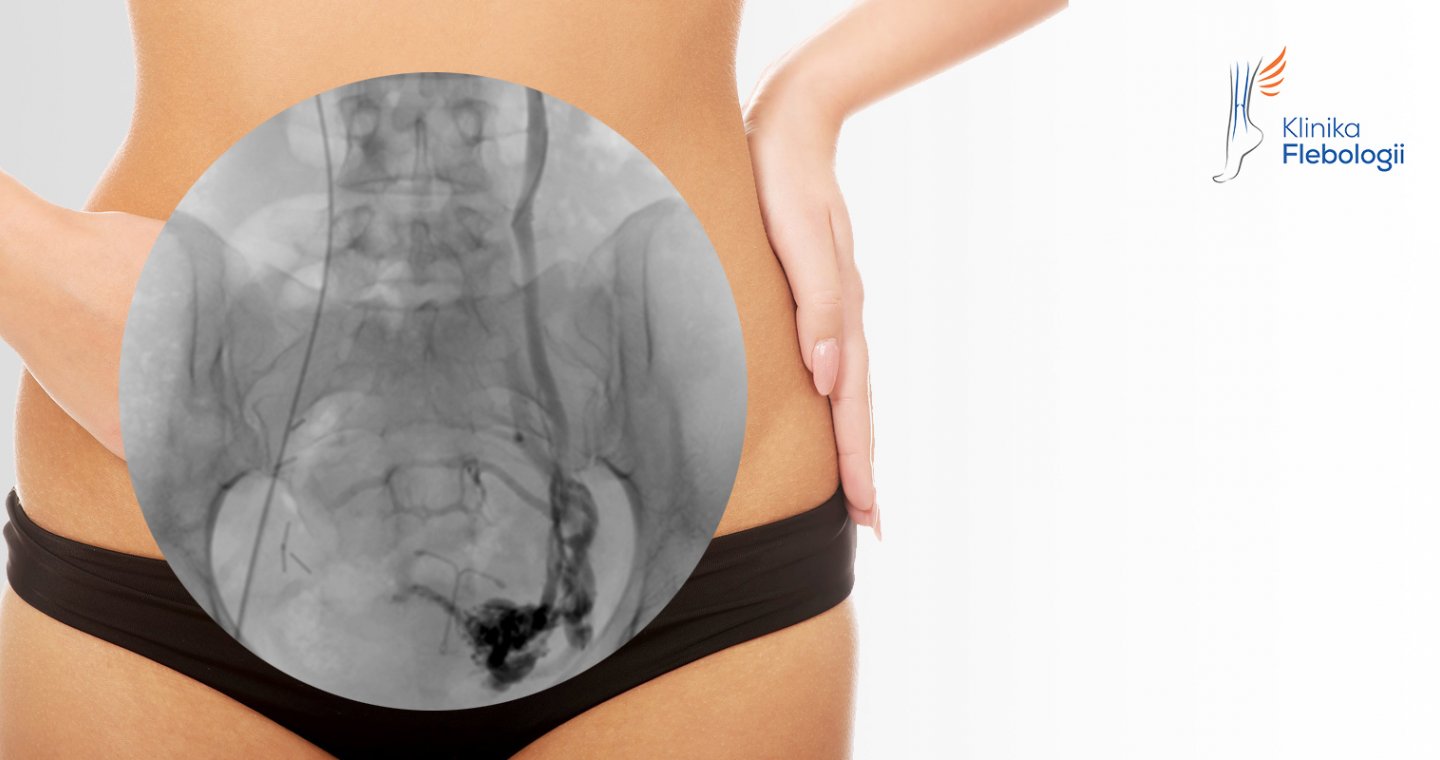

Kluczowe dla leczenia niewydolności żylnej miednicy jest prześledzenie układu chorych żył i ustalenie źródła cofającej się krwi. Nie da się tego zrobić bez dokładnie przeprowadzonej diagnostyki obrazowej.

W tym celu zawsze wykonujemy niezbędny zestaw badań obrazowych, dobierany w sposób indywidualny do każdego przypadku. Proces diagnostyczny rutynowo rozpoczynany jest od badania USG Doppler układu żylnego miednicy i jamy brzusznej w połączeniu z oceną żył okolic intymnych oraz oceną wydolności żylnej na kończynach dolnych. Takie badanie zawsze wykonujemy u pacjentek na czczo, po odpowiednim nawodnieniu w dniu badania.

W pracowni hemodynamiki Szpitala Medicover stosujemy zdecydowanie najczęściej zabiegi małoinwazyjne przeprowadzane drogą wewnątrznaczyniową. Każdy zabieg wykonywany jest pod kontrolą sondy USG i cyfrowej aparatury angiograficznej (tworzony jest tzw. venogram).